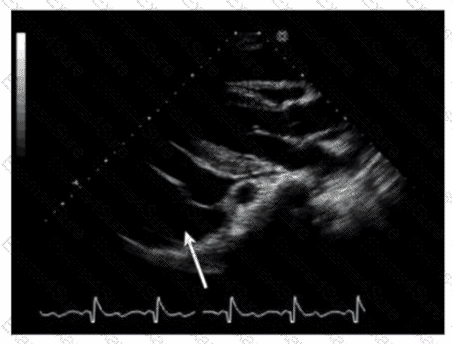

Which is the most likely abnormality represented in these images from a 48-year-old man with shortness of breath?